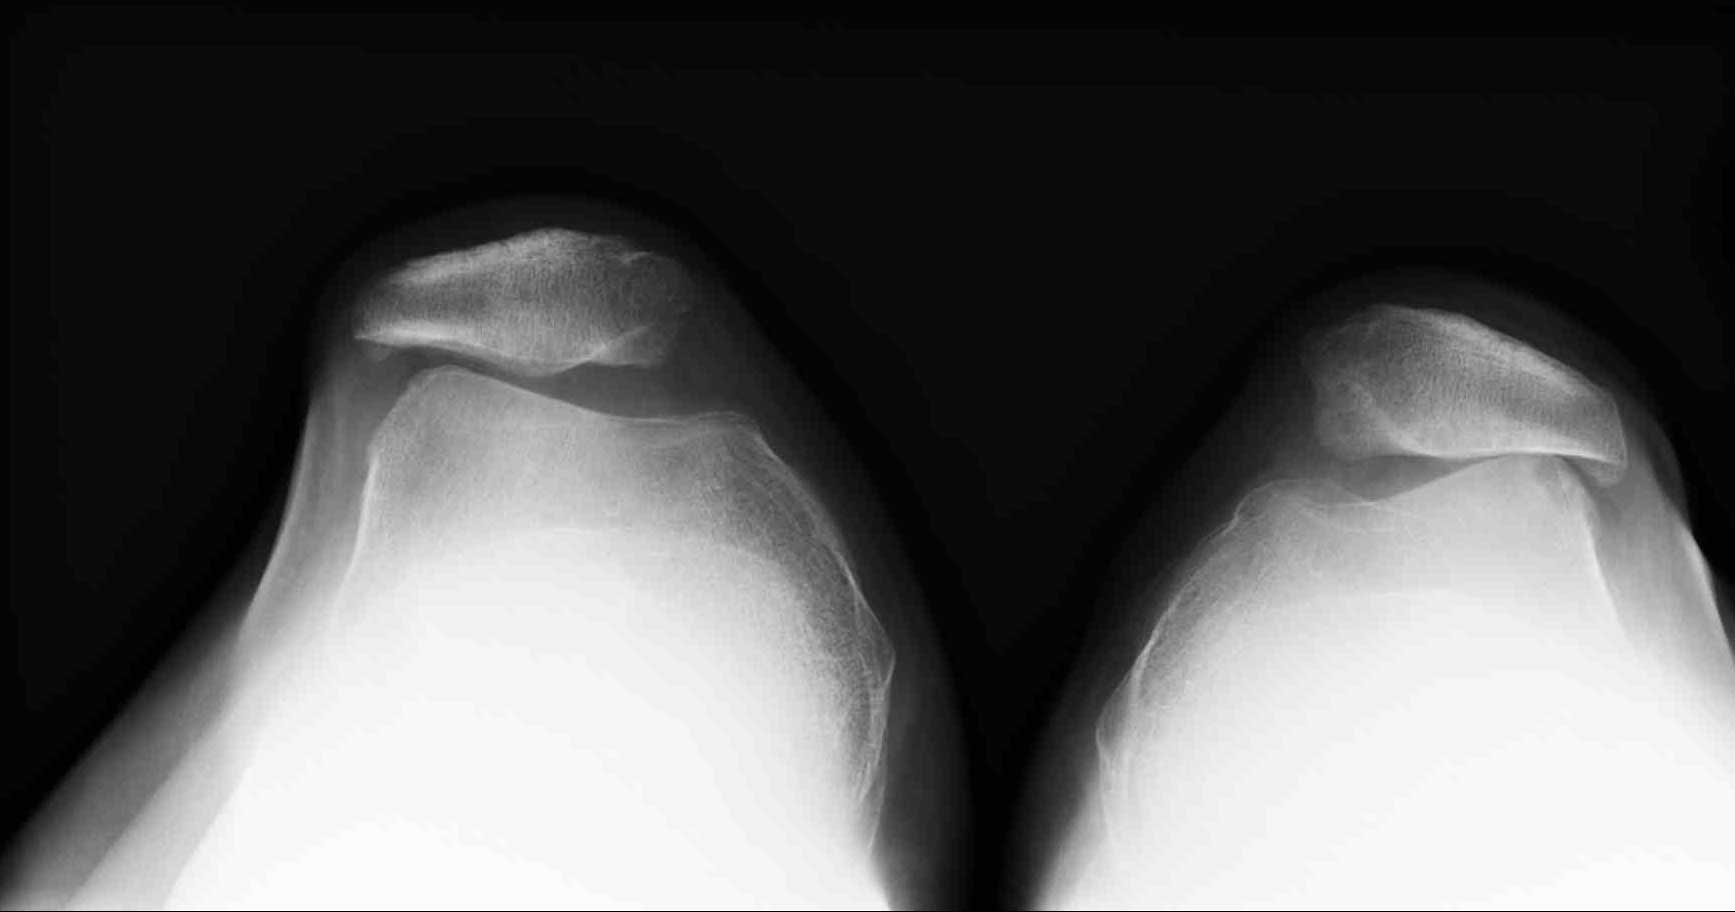

Röntgenaufnahme des patellofemoralen Gelenks

Die Defilee-Aufnahme des Kniegelenks ist das wichtigste Mittel zur Diagnose des Gelenkspaltes im patellofemoralen Gelenk. Dabei liegt der Patient mit angewinkelten Beinen auf dem Röntgentisch. Der Abstand der Patella zur femoralen Gleitrinne kann so ideal dargestellt werden. Ebenso wichtig ist die seitliche Röntgenaufnahme des Kniegelenks. Wenn der Gelenkspalt immer schmaler wird, weist das darauf hin, dass der Knorpel durch eine Fehlstellung (Patelladysplasie) oder Entzündung abgetragen wird.